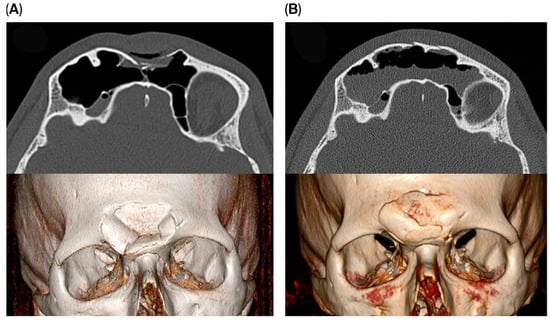

Among patients treated via the endoscopic transorbital approach, four experienced temporary hypoesthesia of the supraorbital nerve one week postoperatively. All cases resolved within a few weeks. One patient developed temporary partial ptosis of the upper eyelid, which resolved approximately four weeks after surgery. In another patient, a residual defect of the anterior wall remained visible as a small external ‘dimple’. Although an additional corrective procedure was proposed, the patient opted against further intervention. All remaining patients achieved satisfactory fracture reduction with no visible residual defects (Figure 3).

Figure 3. Pre- (A) and postoperative (B) images of a patient treated using the endoscopic transorbital approach.